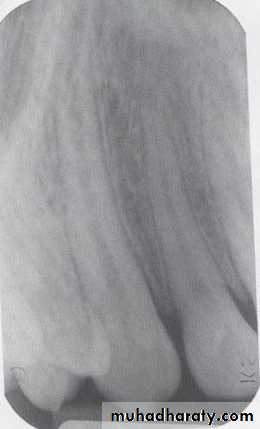

• 2.Position in the jaws:

• - Epicenter coronal to tooth- odontogenic epithelium.

• - Epicenter of the lesion is above the mandibular canal-odontogenic in origin .

• - Epicenter -below lDC- non odontogenic